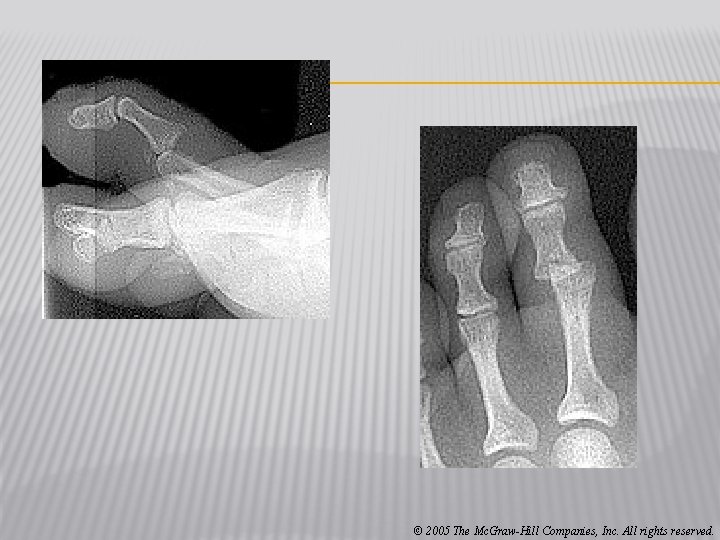

� Fractures and Dislocations of the Phalanges � Cause of Injury � Kicking un-yielding object, stubbing toe, being stepped on � Signs of Injury � Immediate and intense pain � Swelling and discoloration � Obvious deformity with dislocation � Care � Dislocations should be reduced by a physician � Casting may occur with great toe or stiff-soled shoe � Buddy taping is generally sufficient � Shoe with larger toe box may be necessary © 2005 The Mc. Graw-Hill Companies, Inc. All rights reserved.

© 2005 The Mc. Graw-Hill Companies, Inc. All rights reserved.